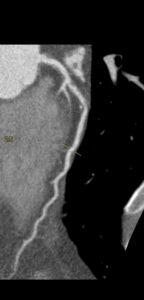

Figurile 1 si 2: reconstrucție multiplanară din examinarea inițială cu evidențierea stenozei severe de la nivelul arterei descedente anterioare (la examinarea coronarografică a fost reclasificată că stenoză moderată și nu a fost stentată)

Figura 3: reconstrucție volumică (VRT) din examinarea inițială cu evidențierea stenozei severe de la nivelul arterei descendente anterioare